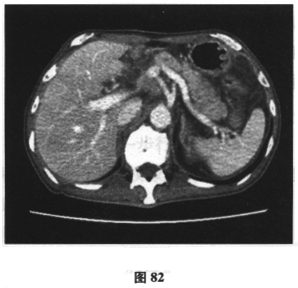

患者男,71岁,因“反复腹胀、纳差6个月,加重伴尿色加重1周余”入院。患者6月前开始肝中上腹胀,进食后加重伴纳差,就诊后予保护胃黏膜治疗症状无缓解。近一月来患者腹胀、纳差较前加重,门诊行胃镜及活检检查示慢性中度萎缩性胃炎伴肠化生,呼气试验示Hp(+),予三联方案(兰索拉唑、左氧氟沙星、克拉霉素)进行Hp根除治疗(该患者青霉素皮试+),停药4周后复查呼气试验示仍(+),调整抗生素后予四联疗法(奥美拉唑、左氧氟沙星、果胶铋、克拉霉素)继续根除治疗,但服药疗程未结束时患者腹胀、纳差加重,伴恶心、呕吐,尿色如浓茶样,伴皮肤黄染,于门诊查肝功能示总胆红素113.7μmol/L,结合胆红素64.5μmol/L,ALT110U/L,AST72U/L,尿常规:胆红素(++)。近2个月体重减轻7.5kg。患者既往于2年前有“肺大疱手术”史,有高血压史6月余,血压最高150/90mmHg,未规律服药。查体:神清,精神尚可,体型消瘦,皮肤巩膜明显黄染,未见肝掌、蜘蛛痣,腹软,无压痛,未及包块,双下肢无水肿。腹部B超未见异常。提示患者进一步检查示肝炎病毒指标、自身抗体均阴性。上腹部增强CT示:胆囊炎,肝内胆管稍扩张(图80),胰腺饱满(图81、图82),肠系膜、后腹膜淋巴结肿大(图83)。胸片显示患者肺部有术后金属物质。根据下面的检查提示,患者可能的诊断是什么?应进一步行何种检查()